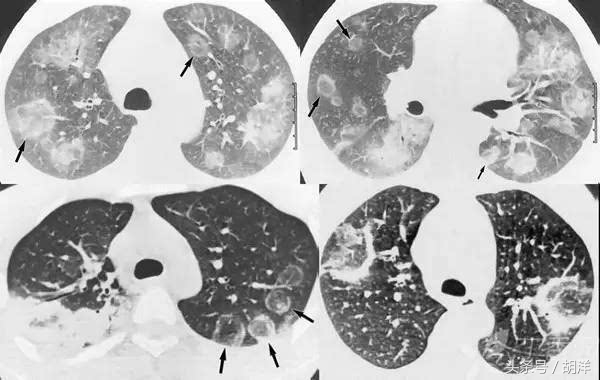

侵袭性肺曲菌病

这种状态是真菌直接感染了没有空洞的肺部,在肺部形成病灶的表现,通常发生于糖尿病、白血病等恶性肿瘤化疗后、长期服用糖皮质激素以及免疫抑制药等免疫力低下的患者,可以在肺部形成团块影、片状影,有的还能形成空洞,在病灶周围还会形成圆形晕征。